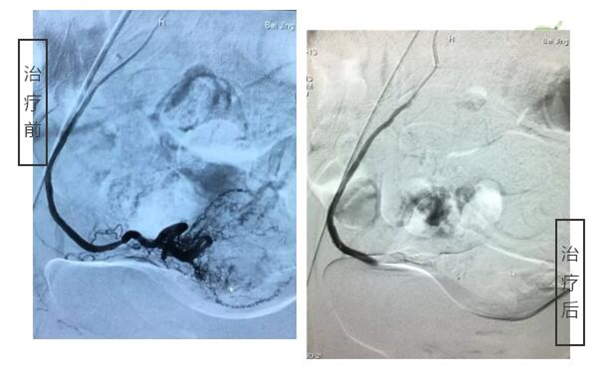

3月13日下午,由血管外科主任何永健主刀,在局麻的状态下,为邰女士实施了介入治疗。整个过程30分钟左右即告顺利完成,患者全程是清醒的,术后即可正常吃喝活动,1-2天便可出院。

左侧子宫动脉

右侧子宫动脉